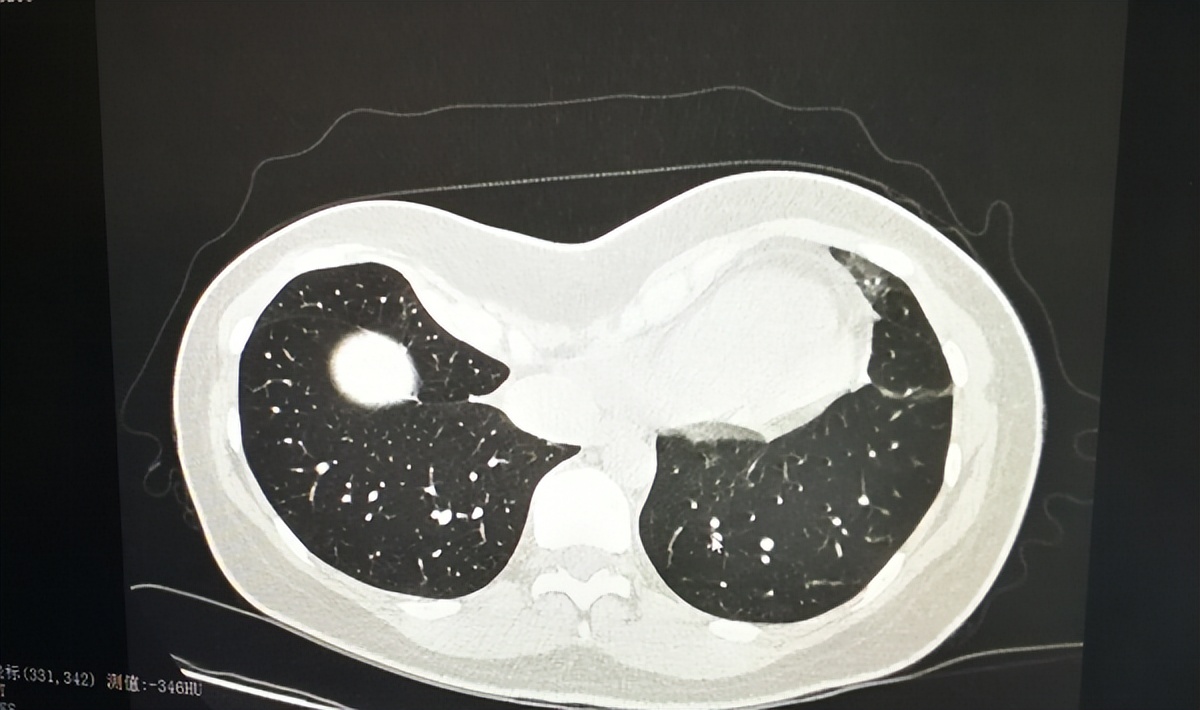

9月20日来院复查时,CT结果显示其肺部炎症已吸收70%,恢复效果显著。该患者的就诊历程,生动印证了“管理式医疗”在实现精准诊断、合理用药和持续随访方面的显著效果。

主诊医生与放射科医生共同阅片分析患者CT,深入讨论病情,确保诊断精准与治疗适配,使主诊医生对肺部炎症程度了然于心,便于指导治疗。